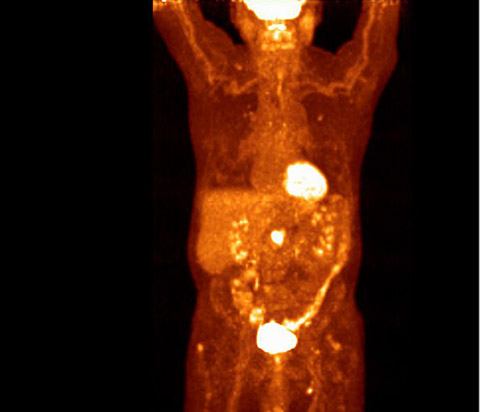

Avec une sensibilité environ deux fois plus élevée qu’un système analogique*, la caméra TEP/TDM Vereos permet une meilleure détection des lésions grâce à une résolution et un contraste améliorés. Constatez la différence de qualité d’image à partir de cette image de thorax. *GEMINI TF 16

Examen d’imagerie TEP numérique Vereos